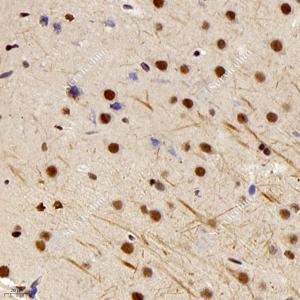

| IHC检测HDAC1蛋白(货号 GB11333). 样品: 大鼠脑, 4%多聚甲醛 (货号G1101) 固定12-24小时. 抗原修复: 柠檬酸抗原修复液(干粉, pH 6.0) (G1201), 98℃, 20分钟. —抗: 1: 300稀释, 4℃ 孵育过夜. 二抗: HRP标记山羊抗兔IgG (H+L) (货号GB23303), 1: 200稀释, 室温孵育1小时. |